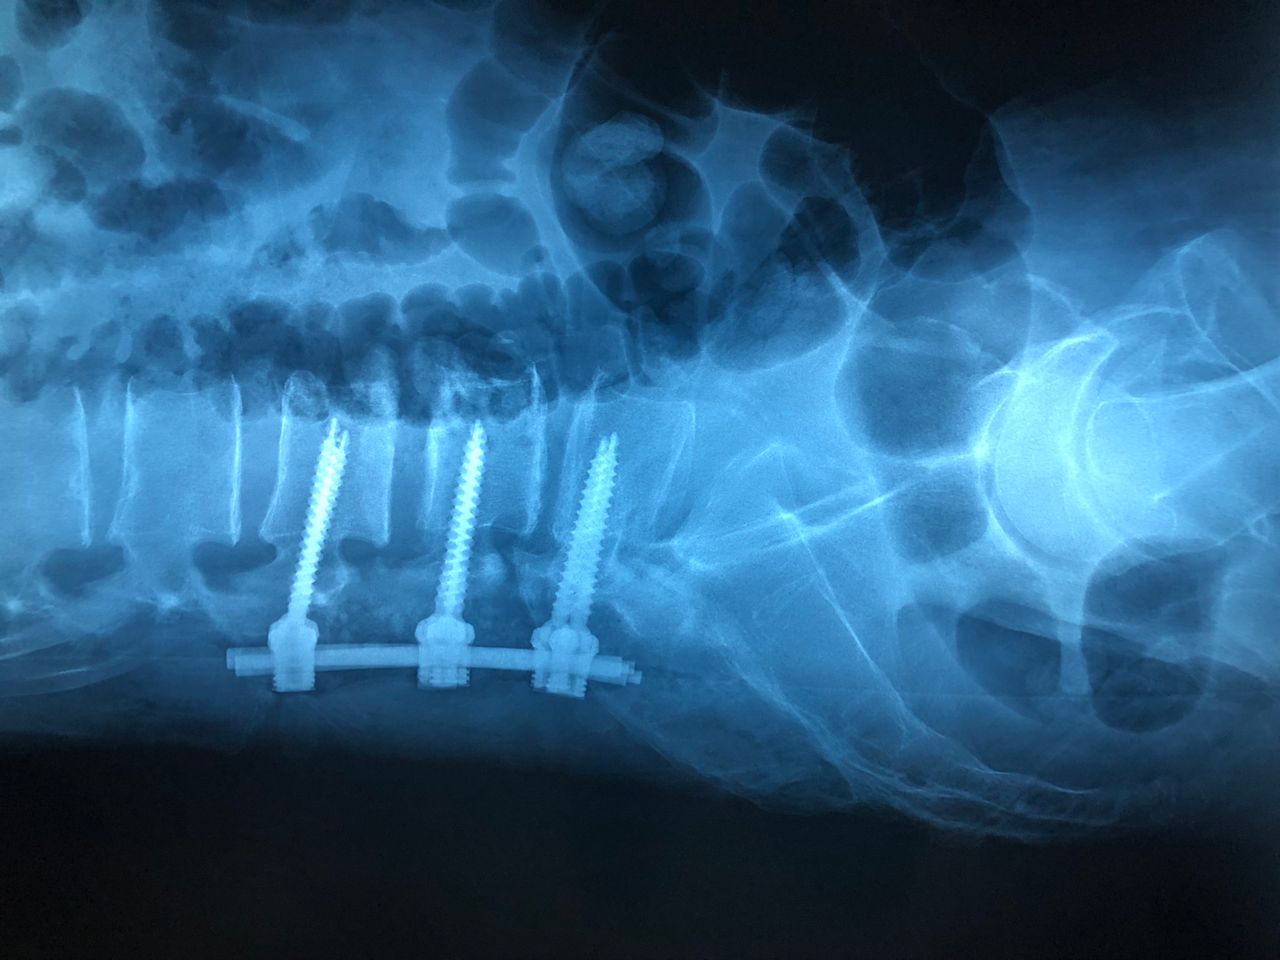

Cirugía de Columna Vertebral (Centro Médico Nacional de Occidente 2016)

• Cirugía de columna